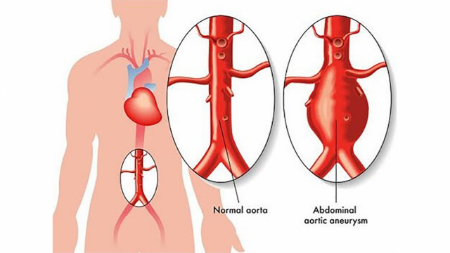

آنوریسم آئورت شکمی چیست؟

آنوریسم آئورت شکمی یک ناحیه بزرگ شده در قسمت پایین شریان اصلی بدن، به نام آئورت است. آئورت از قلب عبور کرده و از مرکز قفسه سینه و ناحیه شکم عبور می کند.

آئورت بزرگترین رگ خونی بدن است. پارگی آنوریسم آئورت شکمی می تواند باعث خونریزی تهدید کننده زندگی شود. درمان بستگی به اندازه آنوریسم و سرعت رشد آن دارد. درمان از چکاپ های سلامتی منظم و آزمایشات تصویربرداری تا جراحی اورژانسی متغیر است.